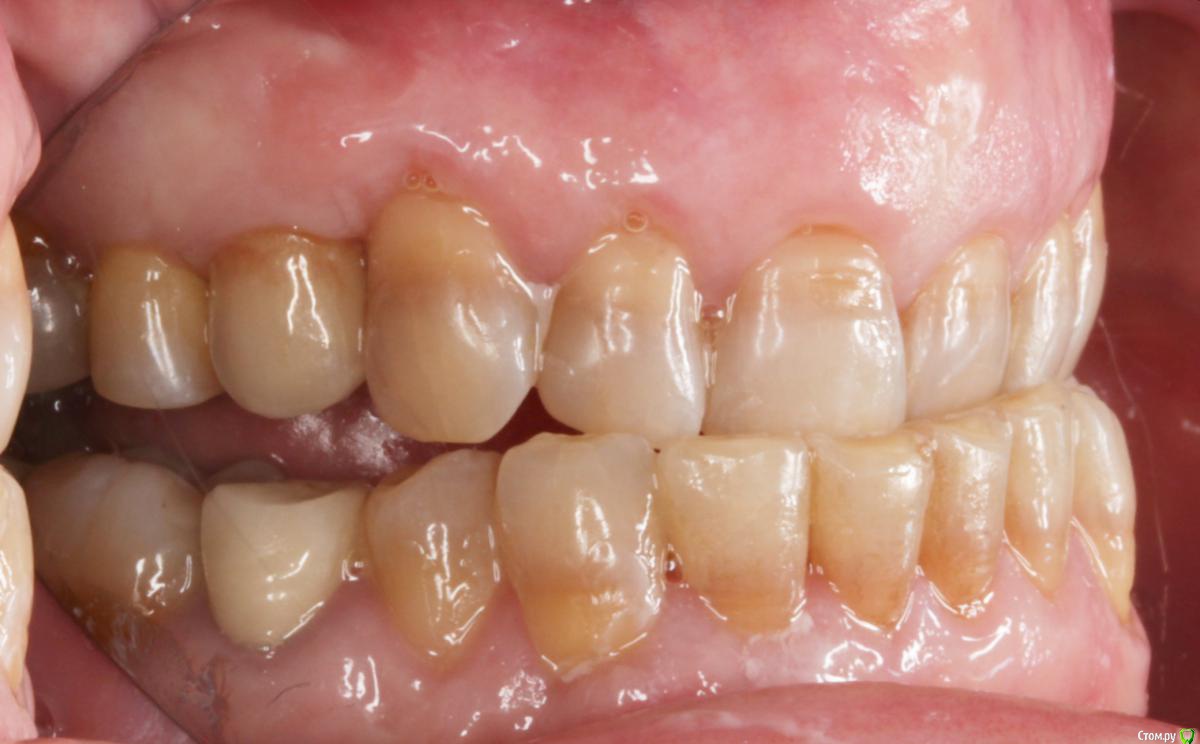

Пациентка пришла с целью восстановления отсутствующих 15,16,17,24,27 з.

Из анамнеза - хронический двухсторонний синусит, соответствующие зубы удалены более 5-ти лет назад, тетрациклиновые зубы ( от изменения цвета отказалась ).